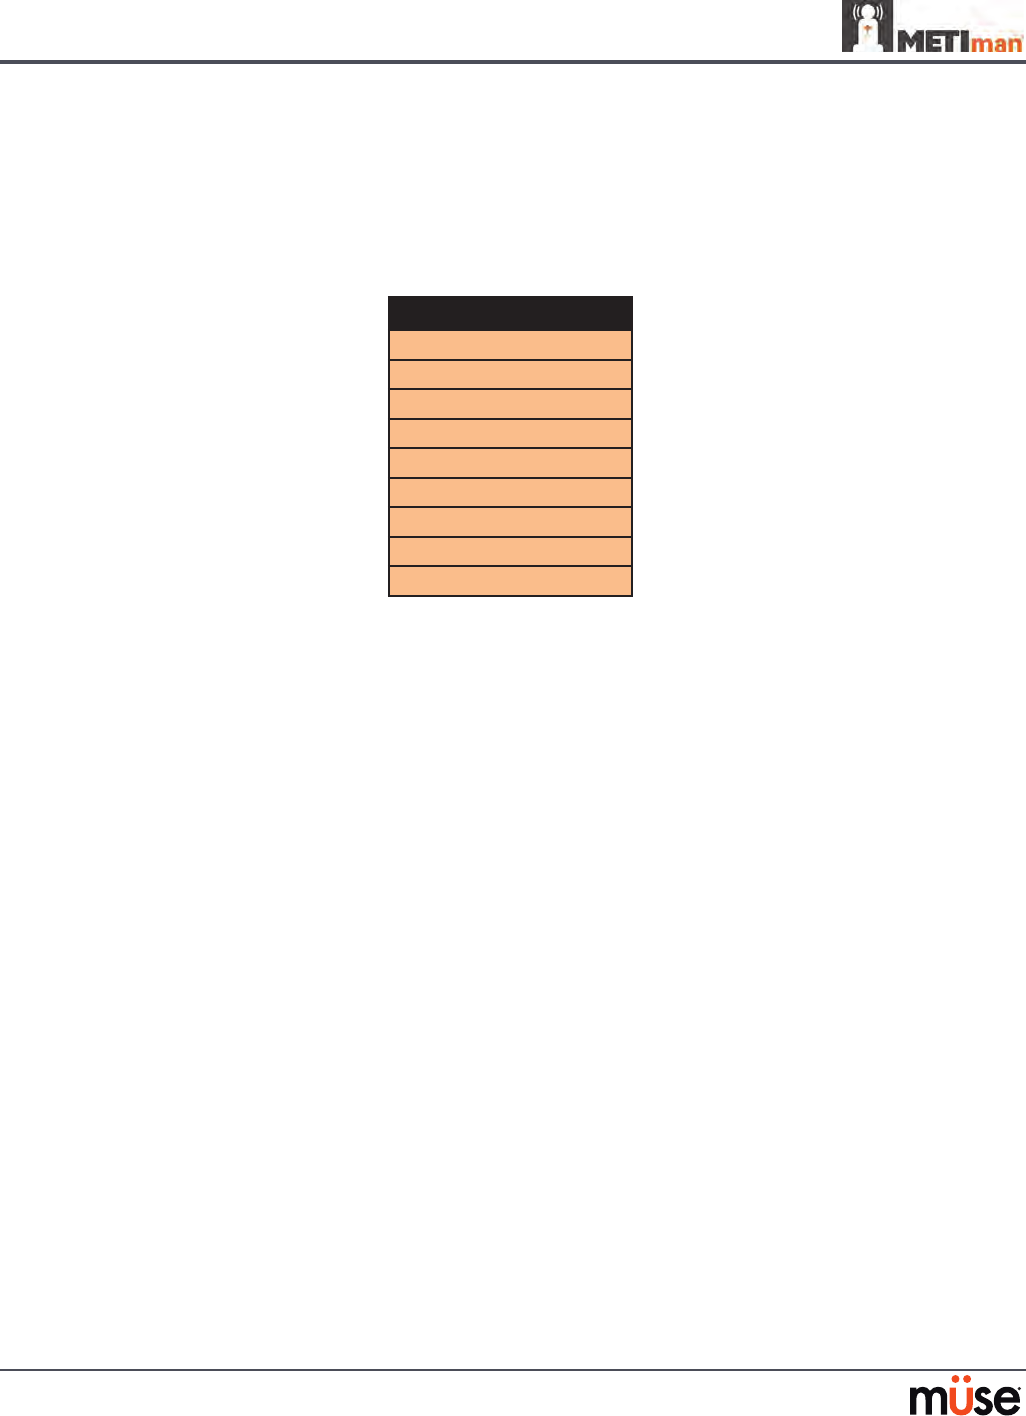

Pulmonary System

Anatomy,

Physiology and

Clinical Signs

Clinical Interventions, Patient Monitoring

and Scenarios.

Software Control

Manual Control

Spontaneous

Breathing

Normal tidal breathing and pathophysiological

conditions such as atelectasis, pneumothorax,

asthma and COPD.

None required, but

adjustable

VIEW: Respiratory

None required.

Exhaled CO2

(Prehospital only)

Measure the presence or absence of CO2 during

positive pressure ventilation.

None required. CO2 canister is

inserted

Pneumothorax or

Hemothorax

Increase in intrapleural volume, leading to

asymmetrical breathing.

None required, but

adjustable

VIEW: Respiratory

CONTROL: Intrapleural

Volume

(Left or Right)

None required.

Chest Excursion Synchronized with ventilation (spontaneous or

positive pressure ventilation). Excursion depth

proportional to tidal volume.

None required. None required.

Breath Sounds Normal and abnormal breath sounds are

independently synchronized with ventilation of

the right and left lungs. Breath sounds can be

auscultated over anterior and posterior anatomic

locations.

None required, but

adjustable

VIEW: Sounds

None required.

Bronchial

Occlusion

Completely obstructs right and/or left mainstem

bronchi, simulating a lower airway obstruction

(e.g. mucus plug). This yields an inability to

ventilate the lungs and asymmetric chest

excursion.

VIEW: Respiratory None required.

Pulse Oximetry Oxyhemoglobin saturation (SpO2) automatically

correlates with the oxygen concentration in the

lungs and the intrapulmonary shunt fraction.

None required, but

adjustable

SpO2 probe is

attached.

Arterial Blood

Gases

PaO2, PaCO2 and pH are continuously calculated,

and the Patient Status Display can be congured

to show them.

None required, but

adjustable

None required.

Venous Blood

Gases

PvO2 and PvCO2 are continuously calculated, and

the Patient Status Display can be congured to

show them.

None required, but

adjustable

None required.